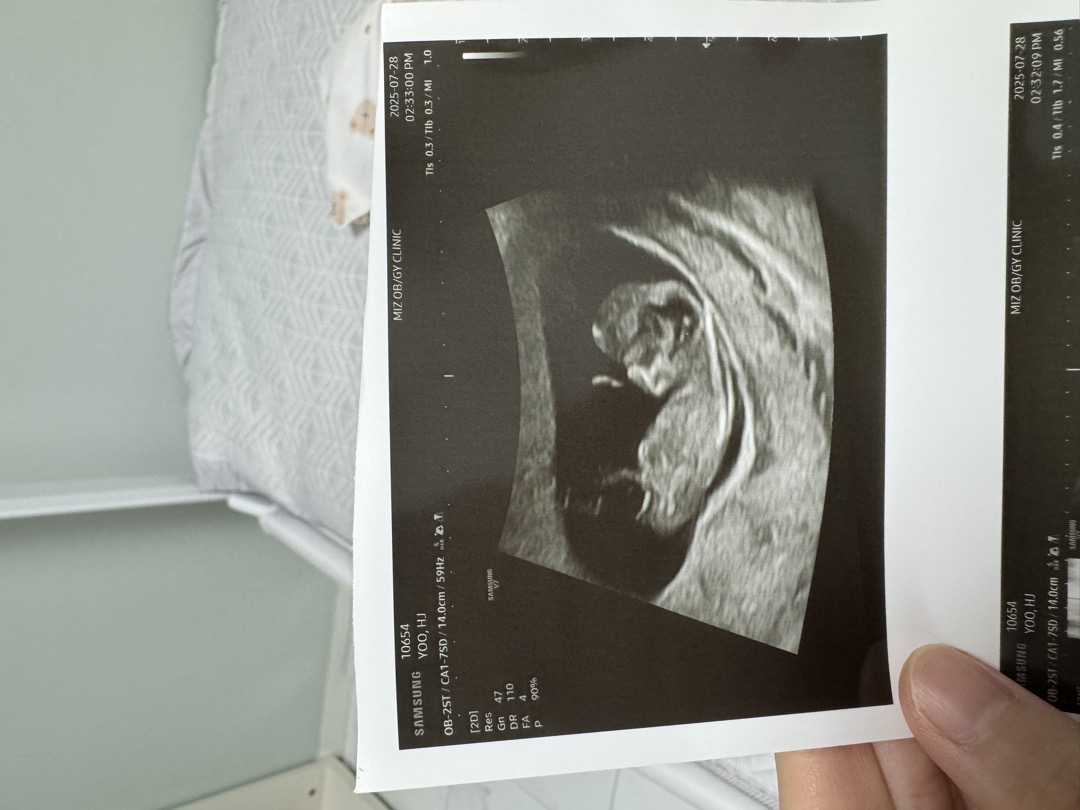

10주 4일 각도법

각도법 궁금해요

아직 각도법 보일 때는 아닌 것 같은데 뭔가 갈라져 보이는 게 딸 같아요!!!ㅋㅋㅋㅋ 발이려나요ㅋㅋㅋㅋㅋ